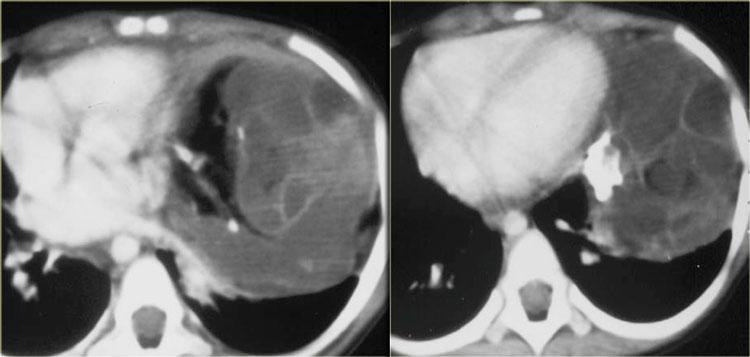

U nguyên bào thần kinh thường có hình thoi, tỷ trọng mô mềm; 50% các khối u lồng ngực có vôi hóa.

U nguyên bào thần kinh phát triển qua nhiều khoang liên sườn và thường xâm lấn ống sống.

Các hình ảnh CT cho thấy một khối vôi hóa ở trung thất sau trải dài qua nhiều đốt sống, xâm lấn vào ống sống.